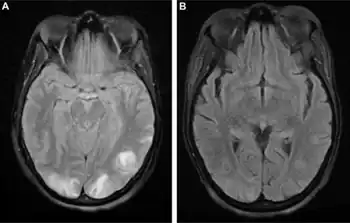

| Posterior reversible encephalopathy syndrome visible on magnetic resonance imaging as multiple cortico-subcortical areas of T2-weighted hyperintense (white) signal involving the occipital and parietal lobes bilaterally and pons. | |

The diagnosis is typically made with magnetic resonance imaging of the brain. The findings most characteristic for PRES are symmetrical hyperintensities on T2-weighed imaging in the parietal and occipital lobes; this pattern is present in more than half of all cases.[1][2] FLAIR sequences can be better at showing these abnormalities.[3] Some specific other rare patterns have been described: the superior frontal sulcus (SFS) watershed pattern, a watershed pattern involving the entire hemisphere (holohemispheric), and a central pattern with vasogenic oedema in the deep white matter, basal ganglia, thalami, brainstem and pons.[1][2] These distinct patterns do not generally correlate with the nature of the symptoms or their severity, although severe edema may suggest a poorer prognosis.[1] If the appearances are not typical, other causes for the symptoms and the imaging abnormalities need to considered before PRES can be diagnosed conclusively.[3] In many cases there is evidence of constriction of the blood vessels (if angiography is performed), suggesting a possible overlap with reversible cerebral vasoconstriction syndrome (RCVS). Diffusion MRI may be used to identify areas of cytotoxic edema caused by poor blood flow (ischemia) but it is not clear if this prognostically relevant.[1][3] Abnormal apparent diffusion coefficient is seen in about 20% of cases.[3]